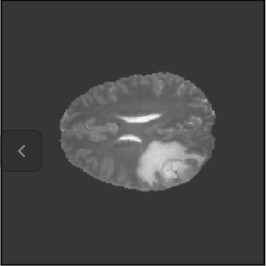

(g) Moving (T2)

Figure 3: Intra and Inter modality MR registration. Time taken: 0.21 sec

To illustrate the performance of the proposed technique for clinical applications, MR images were chosen. The performance of the technique was tested by registering multi-modal MR image pairs. In a clinical setup, it is common practice to register images or volumes acquired from different imaging modalities or MR sequences. Figure 3 illustrates the degree of overlap between moving images (a) T2 and (f) T1 weighted sequence on fixed images (b) T2 and (g) T2 weighted sequence respectively. It was observed using the registration proposed in this manuscript, the dice score improved from 0.44 (prior to registration) to 0.91 (post registration) for multimodal sequences. On the BraTs data, figure 4 (a-d) illustrates the performance of our method based on other metrics such as Dice, SSMI, MI, and MSE respectively. As the key points were generated by utilizing only the feature maps of the initial two layer of the network, the spatial dimension of the data has little impact on the performance. Unlike other CNN based technique which considers the entire image for estimating the transformation parameters, our method requires CoMs which reduces the dimensionality from (m ×\times n ×\times n) to (m ×\times 2), where m denotes the number of feature maps and n is the pixel dimension of the feature map. This aids in lowering execution time drastically. The proposed pipeline also consists of an uncertainty estimator. uncertainty maps illustrated in all the above examples show the region of higher variance in registration, which in turn suggests surgeons/ observers to make better decisions. Pixel region with red color indicates the larger variance region while blue indicated low variance region. For example in figure 3 (e) shows that the central region of the brain has higher pixel-wise variance as compared to the outer part of the brain. The performance of the algorithm on volumes on the same modality is illustrated in figure 3 (a-e)